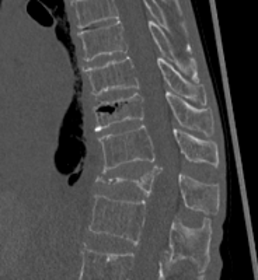

第11胸椎椎体骨折を認めます。骨折部には黒いギャップが存在し、偽関節を呈しています。軽微な後壁損傷も認めます。第1腰椎は椎体骨折後の楔状化変形を認めますが、癒合しています。

骨折部にステントの殻を挿入し、ステント内に骨セメントを充填して治療しました。背中に5mm程度の切開を2か所おいて施します。ステントにより再圧潰が防がれ、また隣接椎体に対する負担も軽減されることが報告されています。